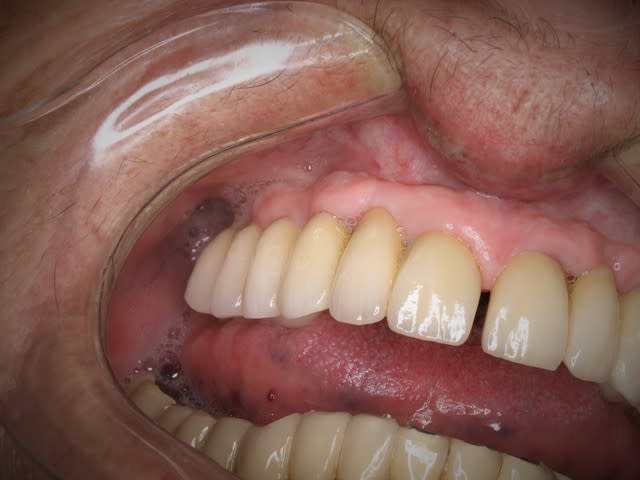

05/01/2016 à 20h29

essayage

la suite,